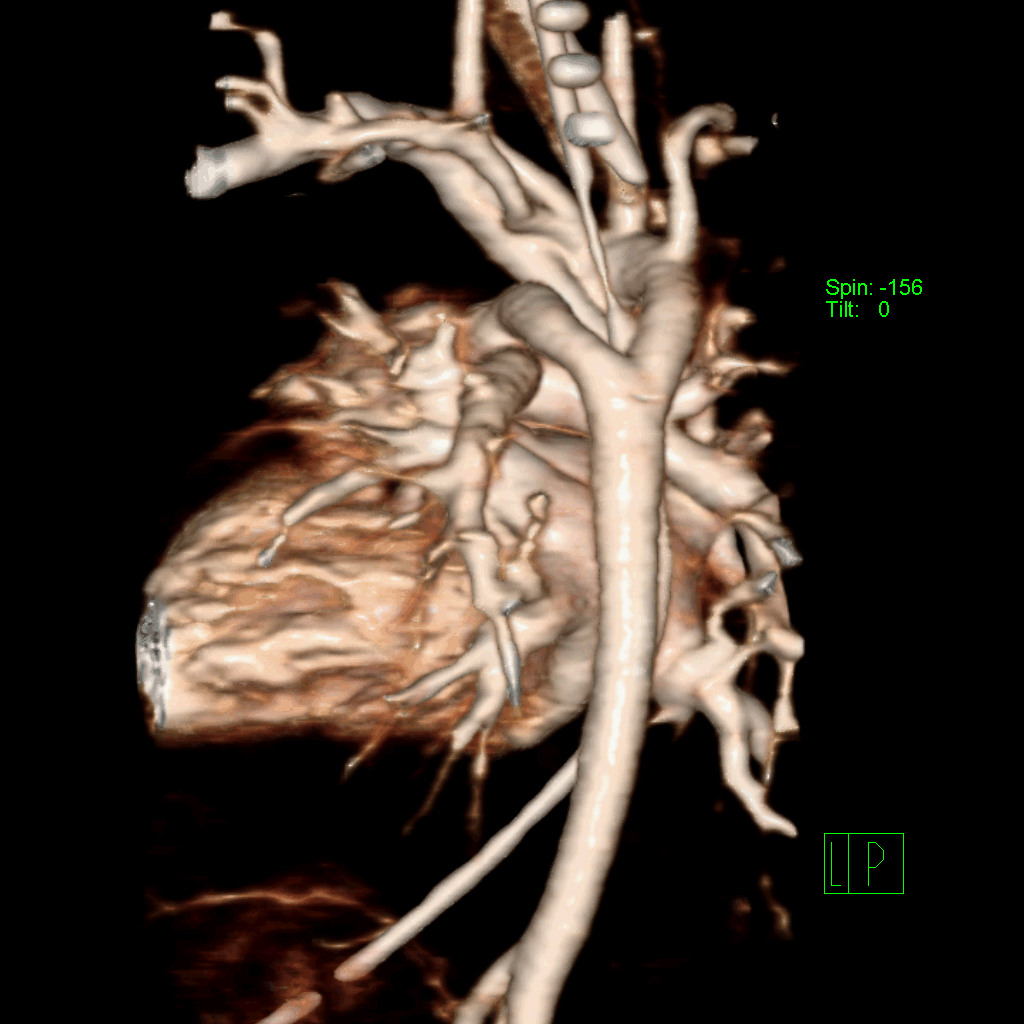

Удвоение дуги аорты. Автор: Бодров Юрий Дмитриевич